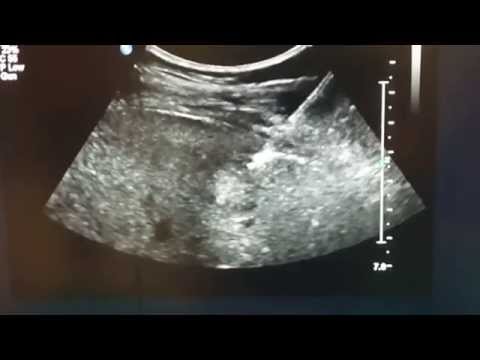

When something may be wrong with your liver, doctors often will order a biopsy to get to the bottom of the problem. Up until now, it’s a procedure that hurts a lot and can be inaccurate, but a new method is being called a game-changer for patients.